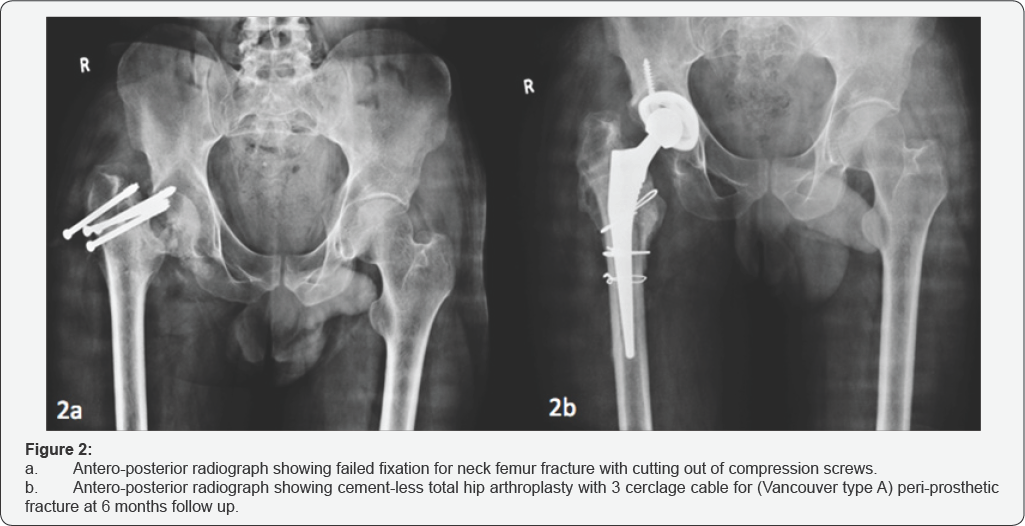

OROAJ.MS.ID.555757